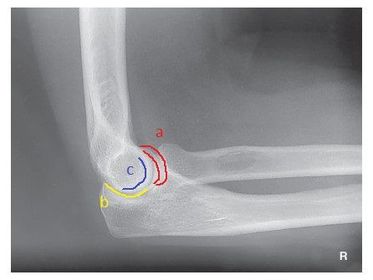

a. outer ridges of capitulum and trochlea b. trochlear notch c. trochlear sulcus

1. trochlear sulcus 2. outer ridges of capitulum and trochlea 3. trochlear notch

C. anterior fat pad D. posterior fat pad E. supinator fat stripe (not visible)

Which fat pad of the elbow will only appear on x-ray if there's a joint pathologic process? Posterior Fat Pad

Why does the elbow need to be in 90 degree flexion to determine whether the posterior fat pad is visible or not? When elbow is flexed more or less than 90 degrees it pushes the fat pad into different position, it can show up on x-ray then when there's no pathologic issue